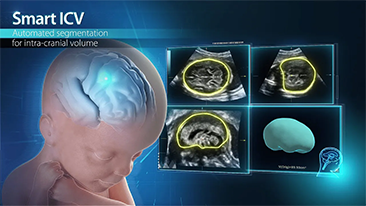

Supportata dalla piattaforma avanzata ZST+, la gamma completa di soluzioni smart di Nuewa ├© progettata appositamente per migliorare la salute della donna durante il periodo pre-gravidanza, la gravidanza e il recupero post-parto, per fornire diagnosi complete ed efficaci e per rispondere a sfide cliniche sempre pi├╣ impegnative.